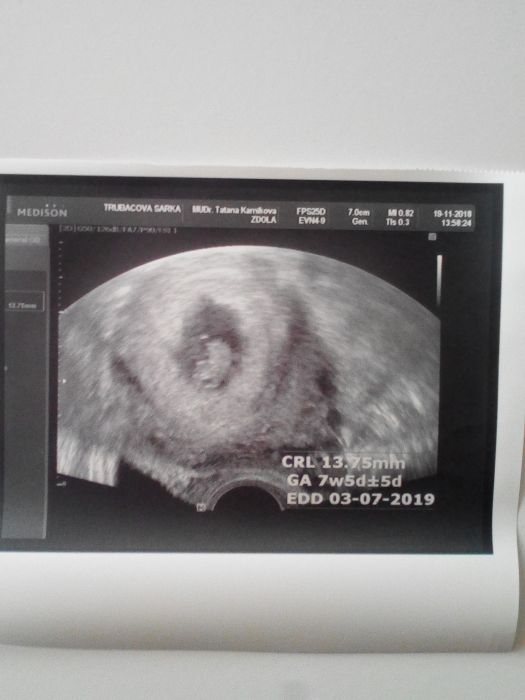

Tak kontrola dopadla na jedničku. Jsme o dva dny starší, dnes tedy 7+5TT a TP zatím 3.7.2019

Srdíčko krásně tluče